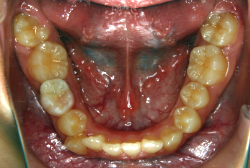

叢生(そうせい)

凸凹な歯並びのことを叢生といいます。矯正歯科に来院する患者様の主訴の中で、最も多いのが「配列の凸凹を真っ直ぐにしたい」というものです。歯の大きさと顎の大きさの調和がとれていないことが原因です。

凸凹を主体としたケースの場合、当院の平均治療期間は18ヶ月ですので、このケースは少し長めに経過しました。理由の一つは凸凹の程度がかなり重症だったと言うことですが、もう一つは、右下第2大臼歯が45度くらい前傾していたため、それを整直化させるために時間を要したと考えています。いずれにしても最終結果は大変よい状態と思います。

治療前は並びが乱れて見た目が悪いというのはもちろん問題ですが、歯科医学的に一番困るのは噛み合わせが悪いという点です。上下の犬歯(3番目の歯)は、上下的に離れた位置にあるため接触することができません。つまり歯としては存在していても、歯としては機能していないということです。